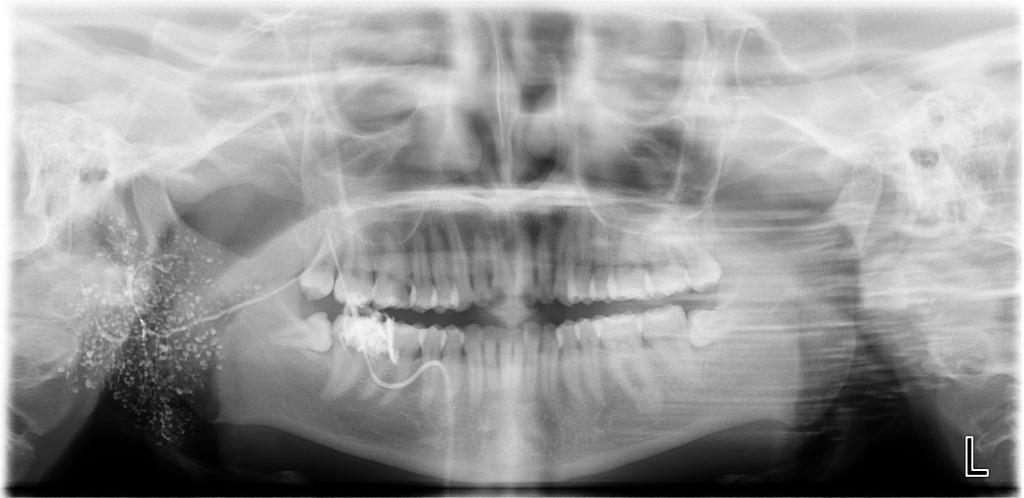

涎腺造影数字化曲面体层片涎腺造影数字化曲面体层片

常规开展:数字化根尖片/横断牙合片、数字化口腔曲面体层片、头影测量侧位/正位片、手腕骨片、颅颌面CBCT、牙齿CBCT的检查以及涎腺造影、窦道 瘘管造影。

诊断范围涉及牙体牙髓病、牙周病、阻生牙/多生牙定位、种植牙术前CT评估分析、颞下颌关节CT诊断分析、,颌骨及涎腺疾病、颌面发育畸形、正畸治疗辅助诊断等大部分颌面部疾病,为临床医疗提供强有力的支持。